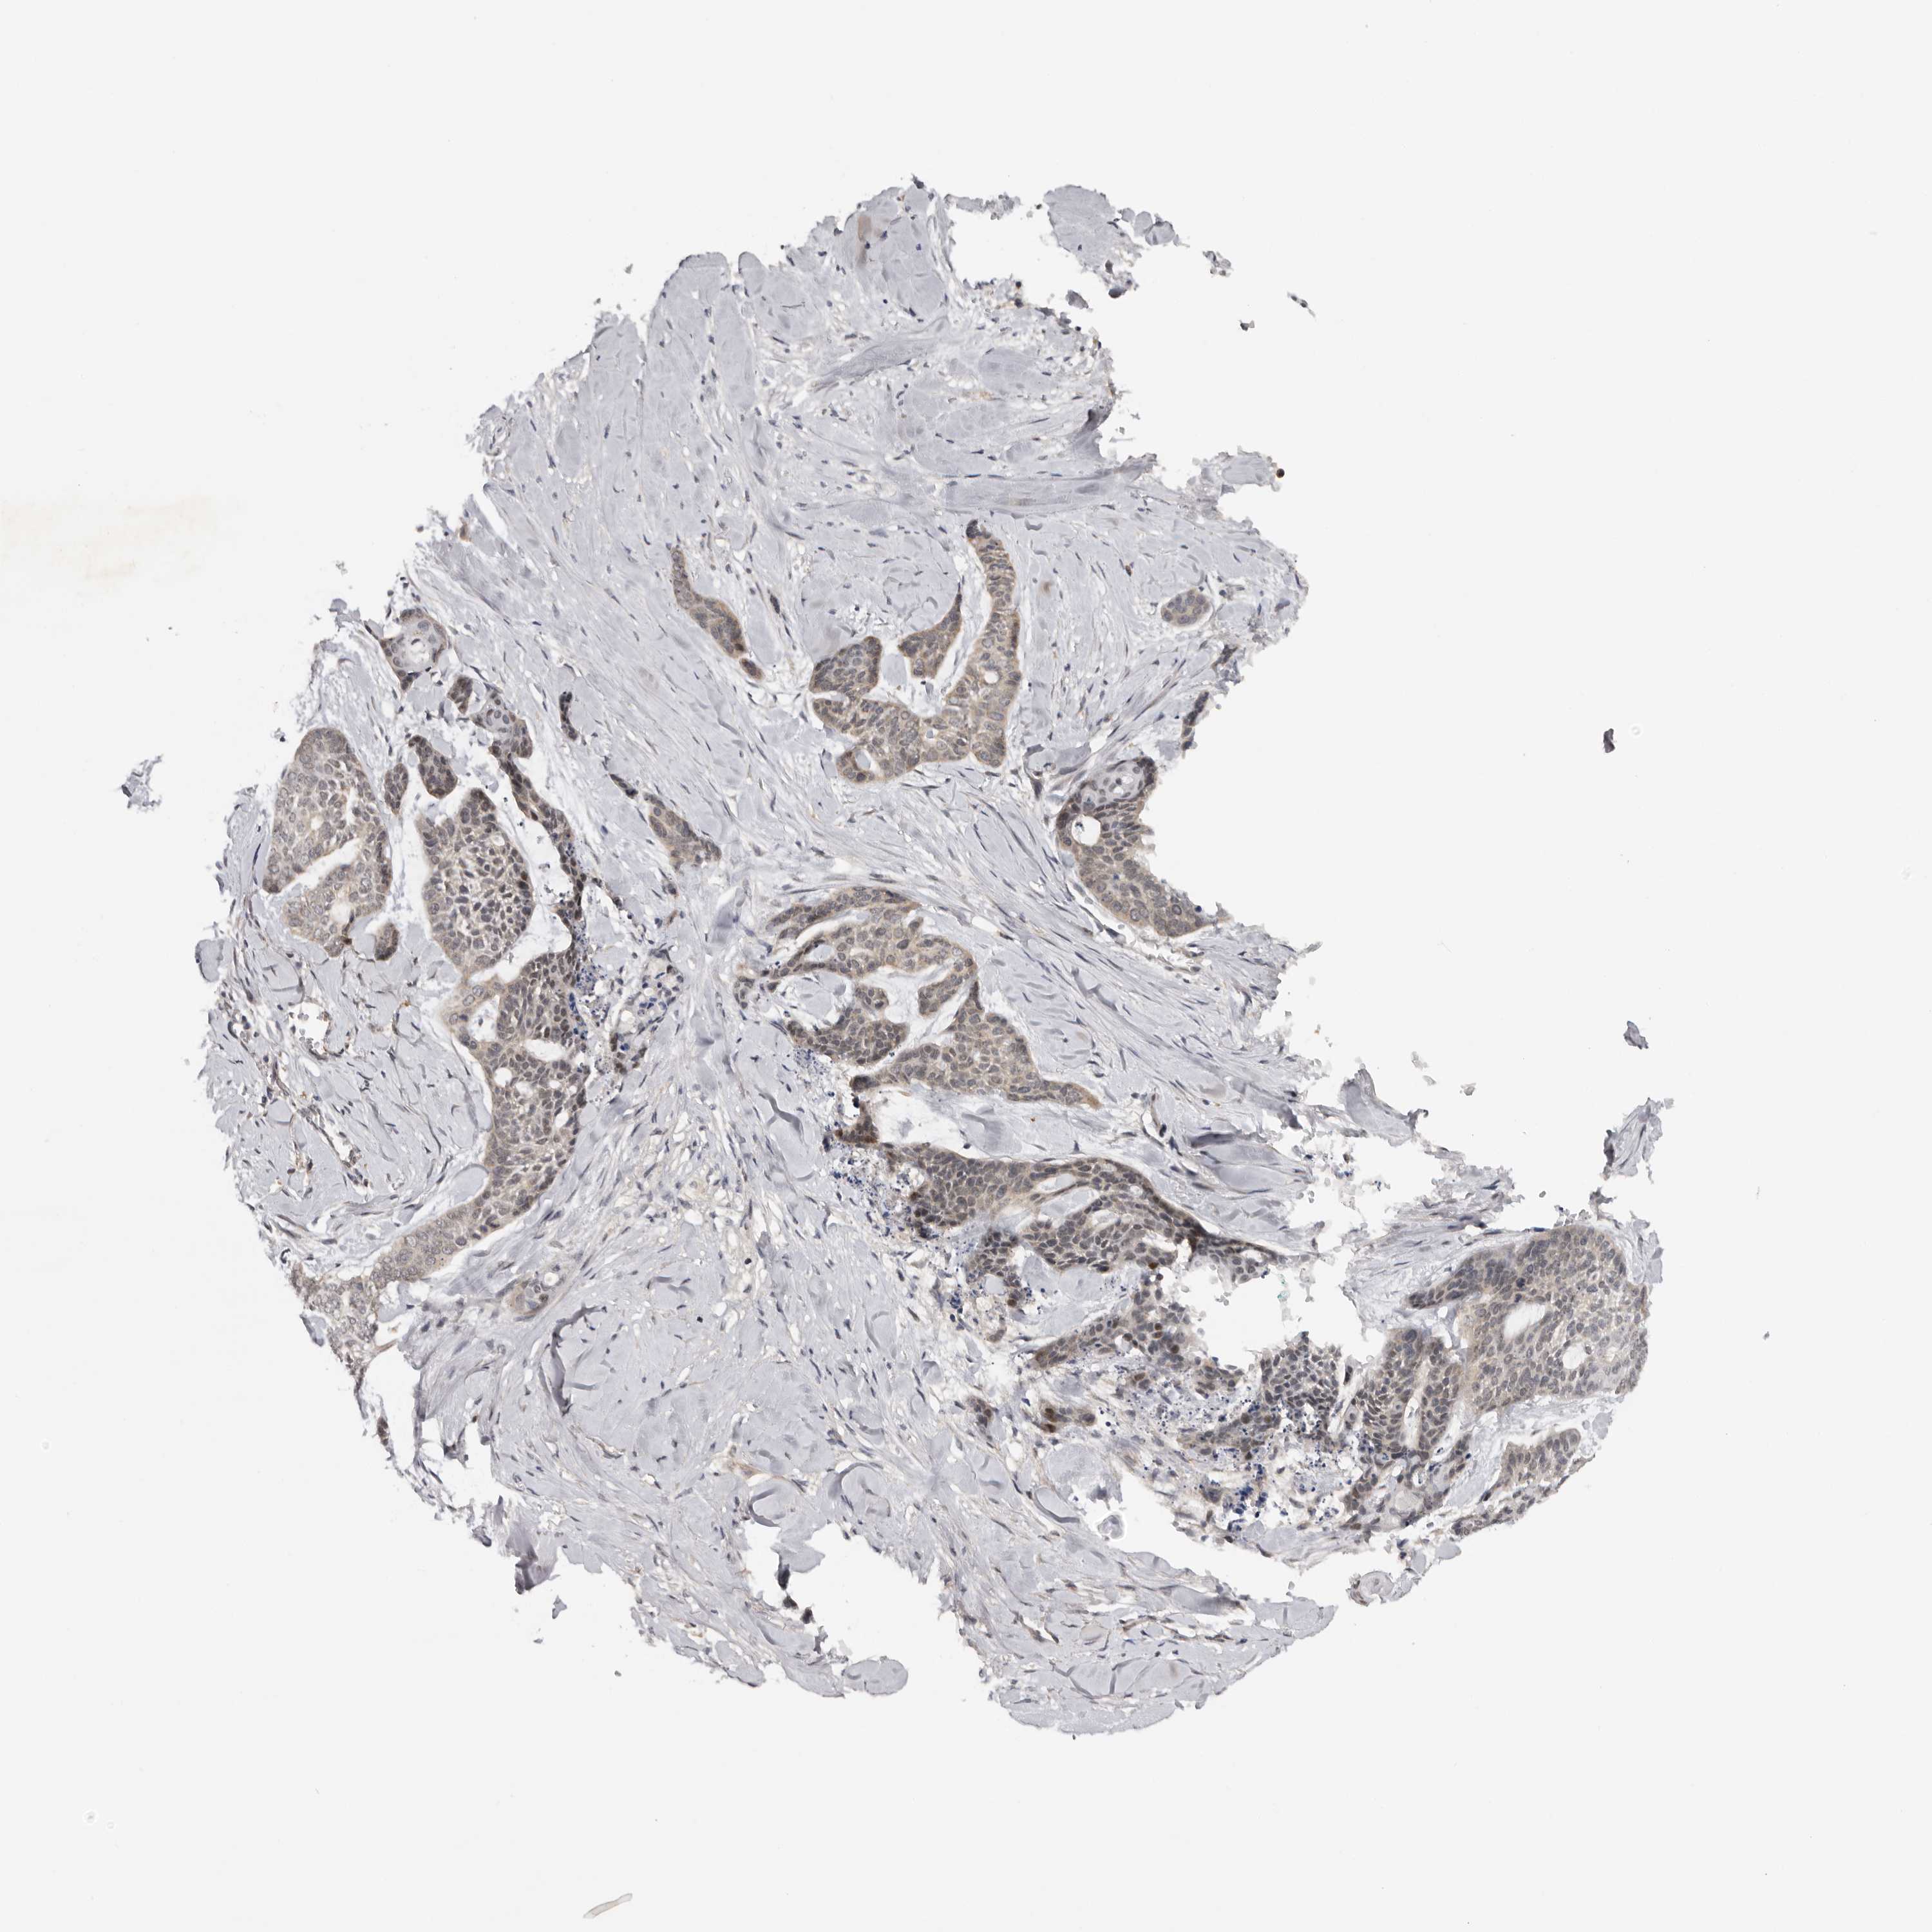

Basal cell and squamous cell cancer

SKIN CANCER - Protein expressioni

A mouse-over function shows sample information and annotation data. Click on an image to view it in a full screen mode. Samples can be filtered based on level of antibody staining by selecting one or several of the following categories: high, medium, low and not detected. The assay and annotation is described here.

Antibody stainingi

Antibody staining in the annotated cell types in the current human tissue is reported as not detected, low, medium, or high, based on conventional immunohistochemistry profiling in selected tissues. This score is based on the combination of the staining intensity and fraction of stained cells.

Each image is clickable and will lead to virtual microscopy that enables deeper exploration of all samples and also displays staining intensity scores, fraction scores and subcellular localization as well as patient and tissue information for each sample.

Antibody HPA023081

Antibody HPA023103

Antibody HPA024795

Staining

High

Medium

Low

Not detected

Intensity

Strong

Moderate

Weak

Negative

Quantity

>75%

75%-25%

<25%

None

Location

Nuclear

Cytoplasmic/membranous

Cytoplasmic/membranous,nuclear

Basal cell carcinoma